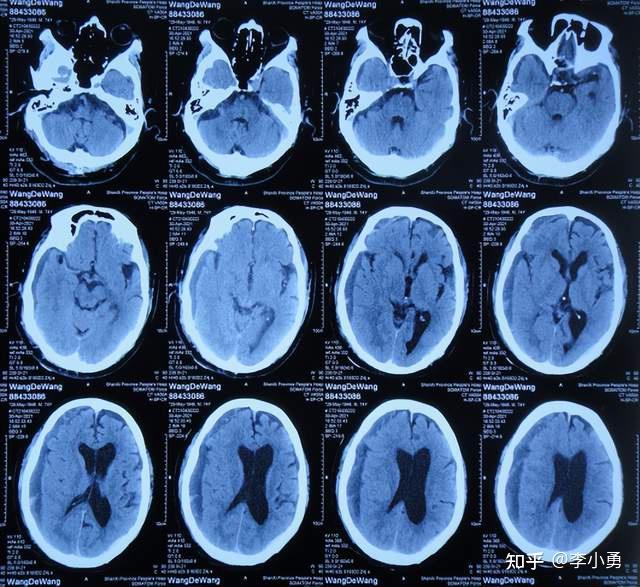

老年正常压力脑积水首次腰大池分流术失败并颅内出血手术,仍脑积水

老年正常压力脑积水首次腰大池分流术失败并颅内出血手术后,在多方